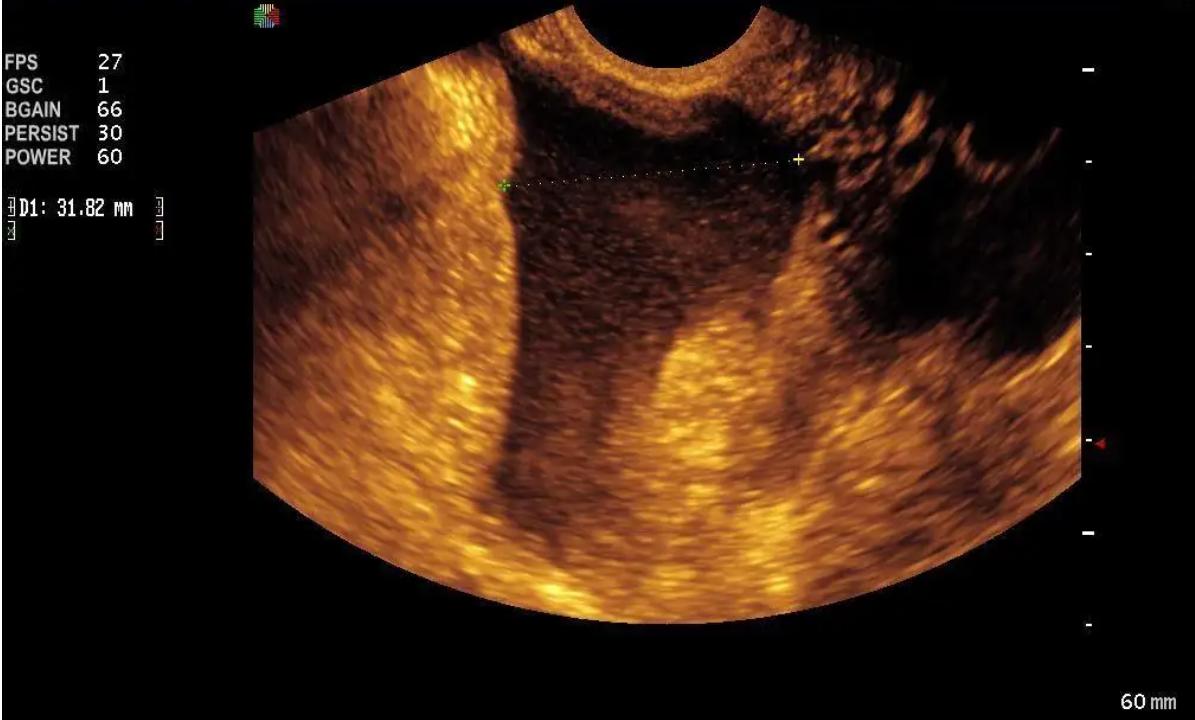

盆腔积液看不到也摸不着,可以通过超声检测来观察,积液深度 小于3cm 属于正常现象。按病理因素可以将盆腔积液分为生理性和病理性两种类型。

主要指卵巢黄体出血、囊肿破裂等。就像盆腔里一个个充满水的气球破裂,导致里面的水全都流到盆腔内。检查时可见附件区包块,且内部回声不均匀,盆腔积液较多。

异位妊娠也就是宫外孕,由于胚胎生长位置的特殊性,会伴有腹腔内大出血的风险。彩超检查显示附件区不均质包块、盆腔积液。